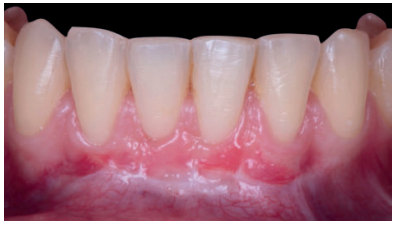

El examen clínico periodontal reveló la presencia de recesión gingival de 5 mm en el diente 31 con una profundidad de sondaje vestibular de 2 mm (perdida de inserción clínica de 7 mm). Presentaba inflamación gingival, además de un frenillo labial inferior insertado en el margen apical de la recesión gingival. El tejido queratinizado faltaba por completo a nivel del diente con recesión (Figura 1). Debido a que el defecto gingival se extendía más allá de la línea mucogingival, así como a la presencia de malposición dentaria, la recesión se categorizó como clase III de Miller6 y RT2 de Cairo7 .

Mujer de 23 años que acudió a nuestra consulta debido a la presencia de múltiples recesiones gingivales desde el diente 32 al 42. La paciente refiere que nota sus dientes más largos, no presenta problemas de hipersensibilidad y había terminado el tratamiento ortodóncico hacía 1 año. La historia médica de la paciente no mostraba datos relevantes. No informó de alergias y no tomaba medicación de ningún tipo. El examen clínico periodontal reveló múltiples recesiones gingivales vestibulares que afectaban a los dientes 32, 31, 41 y 42 (Figura 9), con ausencia de tejido queratinizado apical a las recesiones de los dientes 31 y 32. Tras el estudio radiográfico (Figura 10) se observa pérdida ósea horizontal leve entre los incisivos inferiores (clase III de Miller y RT2 de Cairo).